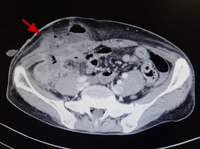

Amebic appendicitis with skin fistula two weeks after appendectomy (enhanced computed tomography).

Original photo from National Center for Global Health and Medicine, Tokyo, Japan.